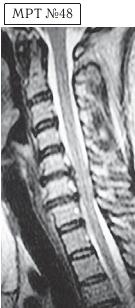

На МРТ № 48 наблюдается сглаженность лордоза, но без кифотической деформации, снижение высоты межпозвонковых дисков, протрузии в сегментах CV-CVI и CVI-CVII, частично компенсированные спондилёзом, выражены краевые остеофиты на данном уровне, абсолютный стеноз и блок ликворных путей, гипертрофия передней и задней продольных связок.